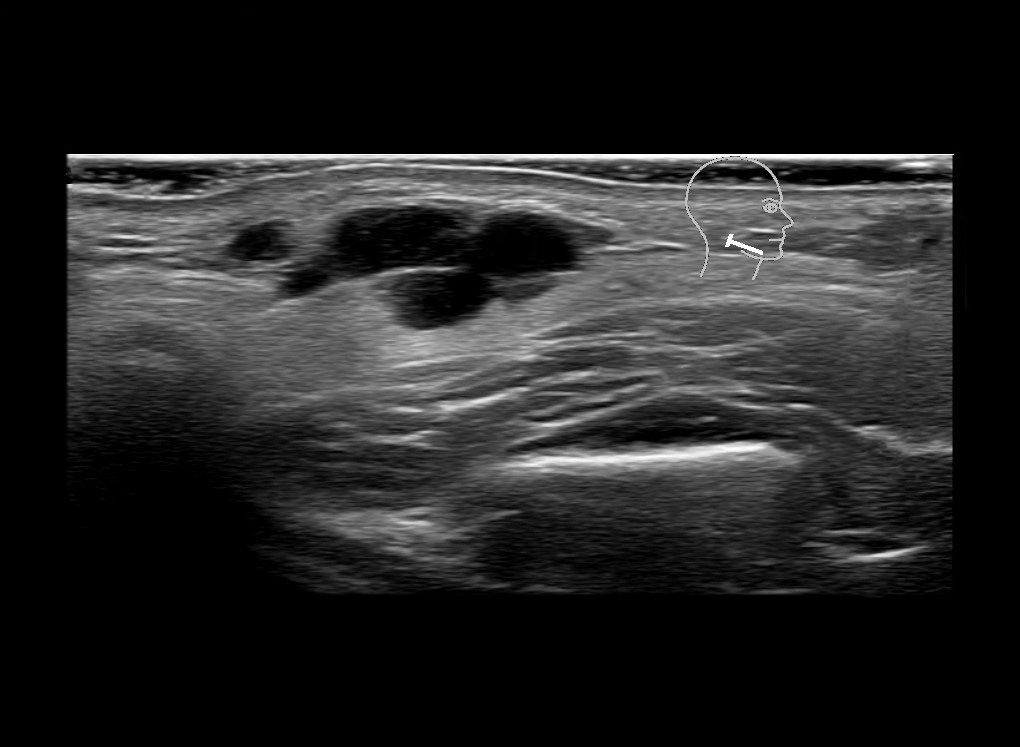

Filler injections in the parotid gland may go unnoticed, however, inflammatory reactions and abscesses may occur. Hypervascularity can be seen with color doppler. Filler deposits are supposed to be injected into the superficial fatty layer . The space to inject into this layer may be limited. Routinely we measure a width of 2-4 millimeters with sometimes subcutaneous layers being less than one millimeter thick.

Study the first image to recognize the different layers. If you are sure about the layers, swipe to the second image to view the answer (if applicable).